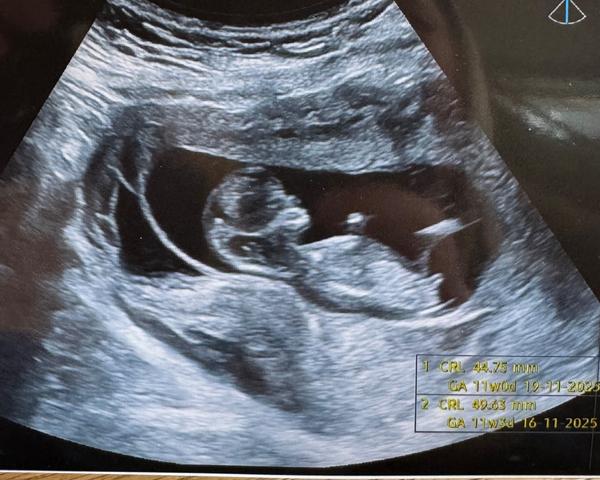

Může někdo určit pohlaví podle ultrazvuku ve 13+3 týdnu?

Prosím co by jste řekli u mě? 😁